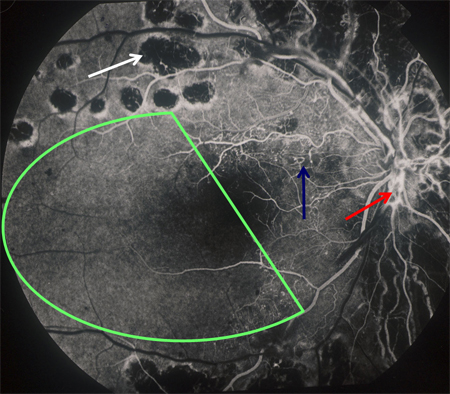

Non-proliferative diabetic retinopathy: intraretinal microvascular abnormality (IRMA; green arrow), venous beading and segmentation (blue arrow), cluster haemorrhage (red circle), featureless retina suggestive of capillary non-perfusion (white ellipse)

Courtesy of Moorfields Photographic Archive; used with permission